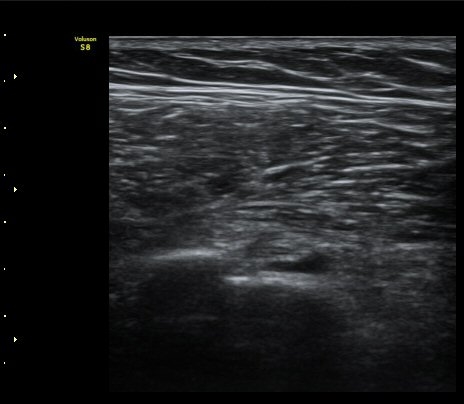

ÃÊÀ½ÆÄ °Ë»ç

¾î±ú À̵ιڱ٠Ⱦ´Ü¸é°Ë»ç¿¡¼­ ½ÉÇÑ Á¡¾×³¶³» ¼ö¾×Àú·ù°¡ °üÂûµÇÁö¸¸ ÆÄ¿öµµÇ÷¯

°Ë»ç¿¡¼­ Ç÷·ùÁõ°¡´Â °üÂûµÇÁö ¾Ê´Â´Ù(±×¸² 1, 2).   À̵ιڱ٠¾Æ·¡ Ⱦ´Ü¸é°Ë»ç¿¡¼­